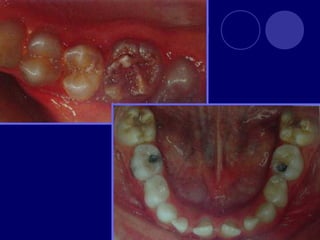

DENTINOGENESIS IMPERFECTA TIPO I:asociada a padecimiento esquelético, asociada a osteogénesis imperfecta (escleróticas azules, sordera, múltiples fracturas,etc.)  Dos denticiones  Dientes blandos, consistencia terrosa  Rx: cámaras pulpares obliteradas

TIPO II:  Dientesde color: amarillo, pardo azulado u opalescente con brillo translúcido, raíces color ámbar  Rx: coronas bulbosas, cámaras pequeñas o ausentes, raíces delgadas y cortas TIPO III: (SHIELDS)  Temporal: translúcido, ámbar  Permanente: normal

OSTEOGENESIS IMPERFECTA Alteración deesmalte y dentina En la dentición temporal no hay esmalte y dentina muy abrasionada En la dentición permanente esmalte frágil color grisáceo y amplias zonas desprovistas de éste, dentina atípica

ODONTODISPLASIA REGIONAL  Dientefantasma  Dientes en forma de concha, pequeños con escasa raíz, amplias cámaras pulpares  Rx: aspecto fantasmagórico